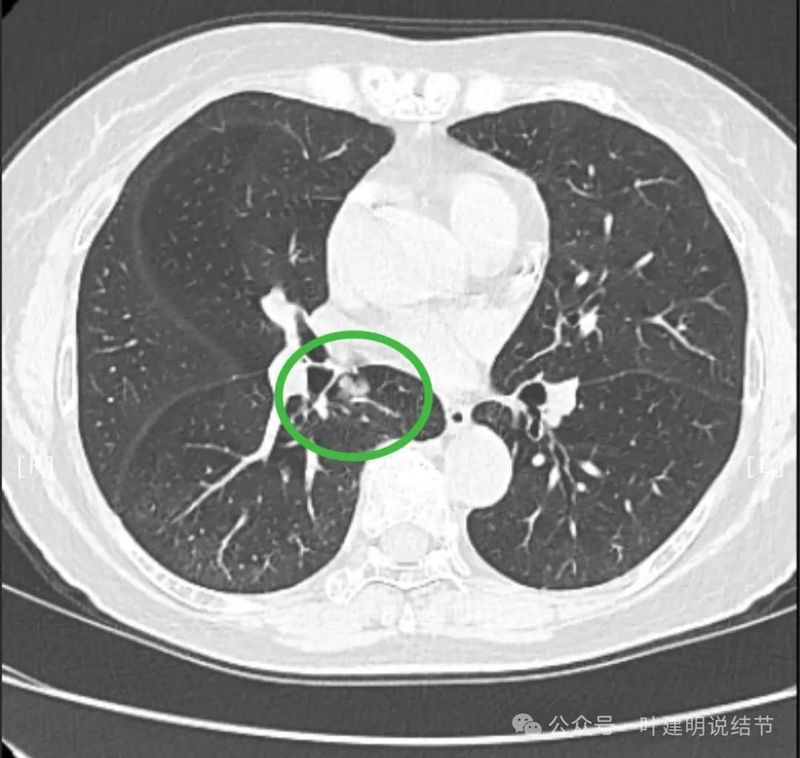

天蓝色箭头示病灶与支气管之间有缝隙,但贴的较近;黄色箭头示支气管管腔;红色箭头示病灶,边缘光滑。

支气管受压,但无明显破坏;与支气管之间紧贴位有的位置仍有缝隙;病灶边缘光滑。

病灶密度较为均匀,对支气管是压迫后移位。表面光滑。

似乎有血管穿过。

边缘光滑,没有毛刺,膨胀性生长。

表面光滑,内部密度较均匀,边界清楚,膨胀性长。

没有侵犯邻近支气管。

边缘光滑,分叶不明显。